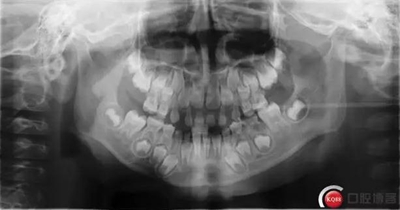

檢查:*75殘冠穿通髓腔,質(zhì)軟,叩診(++),溫度測(cè)試無反應(yīng),X線顯示遠(yuǎn)中根已完全吸收、近中根吸收至根頸1/3,且根尖可見低密度暗影。

診斷:*75牙體缺損+根尖周炎

治療計(jì)劃:*75拔除后制作缺隙保持器